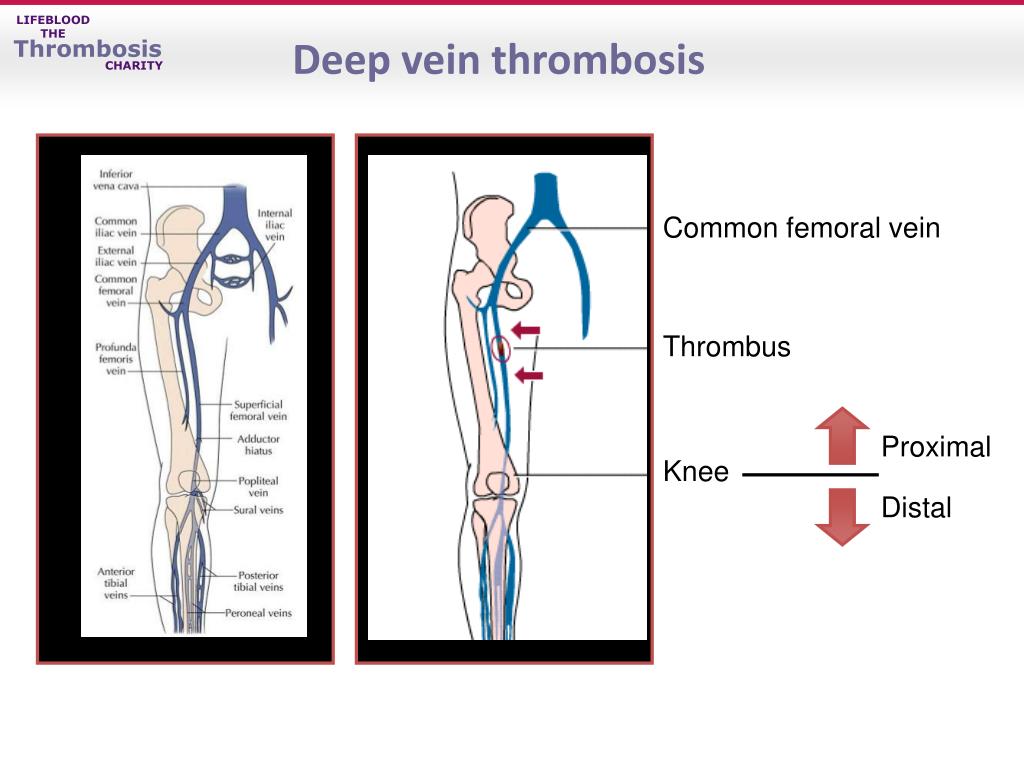

vte distal proximal dvt veins calf

vein thrombosis deep venous thromboembolism treatment prevention femoral common thrombus distal proximal knee ppt secondary powerpoint presentation

vein thrombosis dvt pathophysiology limb rcemlearning rarely typically occur